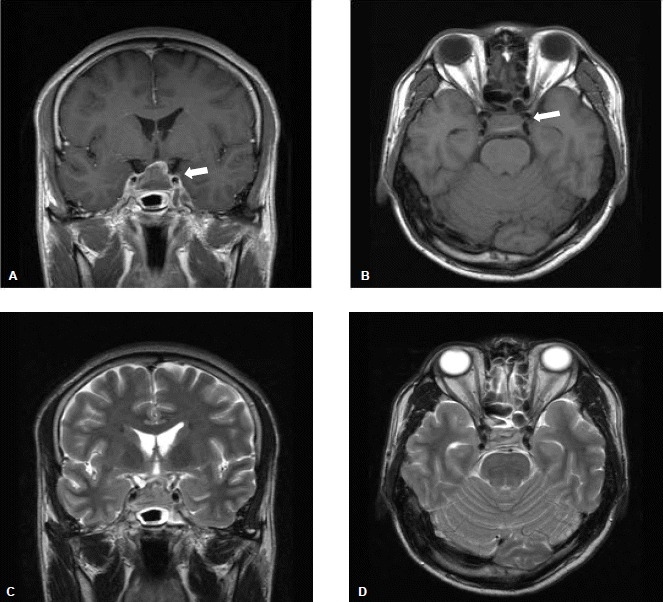

진단 및 경과: 전산화 촬영상 특이소견은 없고, 뇌척수액 검사 소견으로 볼 때 무균성 뇌수막염이 의심되었다. 내원 후 체온 38.3℃로 상승 소견을 보여 수액 및 비스테로이드소염제 투여 등의 보존적 치료를 시행하였으며 내원 전일부터 중단한 프레드니솔론은 재투여하지 않았다. 내원 3병일 두통, 오심 및 발열이 지속되며 복시를 호소하였으며 신경학적 검사상 안구 운동 장애는 뚜렷하지 않았으나 적유리 검사(red glass test) 양성으로 양측성 6번 뇌신경 마비가 의심되어 입원 5병일 뇌 자기 공명 영상검사 시행(그림 2), 2.5×2.2 cm 크기의 내부 출혈이 동반된 거대 뇌하수체 종양이 우측 해면 정맥동으로 확장된 소견을 보여 뇌하수체졸증으로 진단되었다. 부신 위기 가능성 고려해 프레드니솔론 500 mg 정맥 투여를 시행 후, 입원 7병일 복시가 소실되며 발열이 소실되고 전신 증상이 호전되는 양상을 보였다. 투약 전 오전 8시에 시행한 뇌하수체 기저 호르몬 검사상 cortisol 0.6 μg/dL, ACTH 40.51 pg/mL 및 freeT4 0.76 ng/dL, TSH 0.16 μIU/mL로 뇌하수체 기능저하증 동반이 의심되어 임상 증상 안정 후 주사제를 경구 프레드니솔론 7.5 mg으로 변경, 유지하였으며 스테로이드 투여 3일 후 레보티록신 50 μg을 추가하였다. 이후 free T4 0.94 ng/dL, TSH 0.6 μIU/mL로 정상 갑상선 기능 상태에서 입원 23병일째 경접형동 접근법으로 병변을 제거하였고, 조직 검사를 통해 출혈성 경색을 동반한 뇌하수체 선종을 진단하였다(그림 3). 수술 4주 후 시행한 복합 뇌하수체 자극 검사를 시행하였으며 결과는 표 2와 같다. TSH는 기저치 1.29 μIU/mL, 90분 후 최고치가 4.46 μIU/mL로, cortisol의 경우도 기저치 7.08 μIU/mL, 60분 후 최고치가 9.83 μIU/mL로 자극에 둔화된 반응을 보였으며, 이외 GH, LH, FSH의 반응도 감소된 소견을 보여 뇌하수체 기능저하증으로 진단할 수 있었으며, testosterone 또한 0.08 ng/mL (정상치: 2.12~7.60)로 저하되어 hydrocortisone 20 mg과 레보티록신 50 μg 투약 및 testosterone enanthate 100 mg 근주를 시행하였으며 이후 특별한 증상 없이 치료 유지하며 외래에서 경과관찰 중이다.

Figure 2.

T1-weighted (A, B) and T2-weighted (C, D) MRI shows an inhomogeneous pituitary mass (indicated by the white arrow) consisting of an enhanced upper portion and non-enhanced lower portion shown by iso and low signals in T2-weighted images suggesting a hemorrhagic pituitary mass.